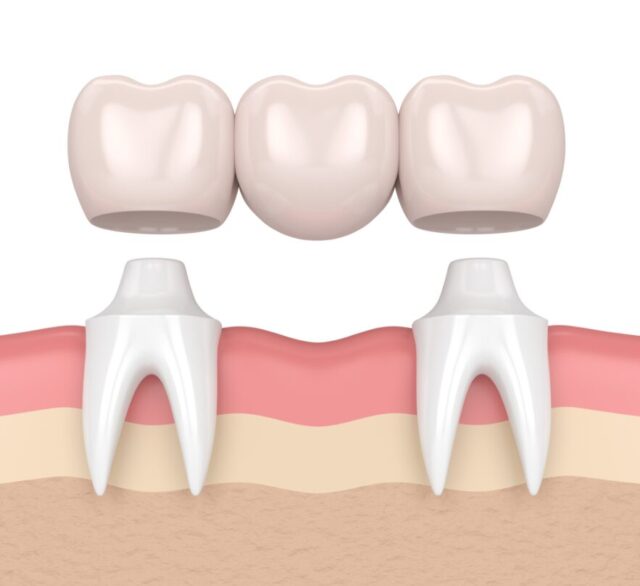

Một chiếc cầu răng tiêu chuẩn thường bao gồm ba phần chính:

- Mão răng (Crowns): Là hai chiếc răng sứ được thiết kế để đặt lên hai chiếc răng thật khỏe mạnh ở hai bên khoảng trống mất răng. Hai chiếc răng này đóng vai trò như trụ cầu, hay còn gọi là trụ đỡ.

- Nhịp cầu (Pontic): Là chiếc răng giả nằm giữa hai mão răng, có nhiệm vụ lấp đầy khoảng trống của chiếc răng đã mất. Chiếc răng này được thiết kế sao cho có hình dáng và màu sắc giống hệt với răng tự nhiên.

Nguyên tắc phục hình của cầu răng là sử dụng các răng thật khỏe mạnh lân cận làm điểm tựa để nâng đỡ và giữ chắc chiếc răng giả ở vị trí bị khuyết. Để làm được điều này, nha sĩ sẽ mài nhỏ hai chiếc răng trụ để làm cùi răng, sau đó gắn mão răng và nhịp cầu lên trên.